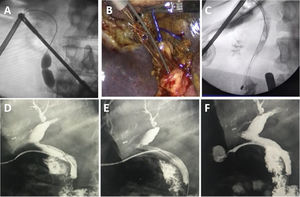

Técnica quirúrgicaColocación de puertos modificadaLa ubicación de los puertos que utilizamos para la colecistectomía laparoscópica es la clásica americana, con el cirujano a la izquierda del paciente. En los casos en que sospechamos coledocolitiasis, y anticipando la necesidad de realizar puntos intracorpóreos, consideramos que la ubicación óptima del puerto epigástrico es a la izquierda de la línea media y del ligamento redondo, en el hipocondrio izquierdo, lo que nos permite tener una mejor angulación para maniobras avanzadas (fig. 2A).

Ligadura de conducto cístico y nueva cisticotomíaAnte una sección total involuntaria del cístico tras la cisticotomía, intentar retomarlo con una pinza para introducir un catéter de colangiografía o una canastilla suele ser dificultoso, especialmente cuando la longitud residual es corta. Una manera sencilla de resolverlo consiste en ligar el conducto seccionado con un nudo preformado tipo endoloop y traccionar del mismo para realizar una nueva cisticotomía y posterior reintroducción de un catéter (fig. 2B).

La maniobra que utilizamos consiste en atrapar el cálculo con la canastilla, arrastrarlo hasta el cístico y ampliar la cisticotomía sobre el cálculo (fig. 2C).

La apertura vesicular sobre la cara quirúrgica permite extraer el cálculo y lograr una tracción adecuada (fig. 2D). Esta maniobra puede ocasionar en algunos casos una dificultad agregada por la caída de cálculos en la cavidad peritoneal, por lo que la utilizamos solamente en casos seleccionados de gran dificultad, como el síndrome de Mirizzi tipo 1.

En estos casos es necesaria una nueva disección del conducto más próximo a la vía biliar principal, permitiendo rectificar el trayecto, realizar una nueva cisticotomía y facilitar su canalización e instrumentación posterior (figs. 4A y 4B).

Extracción de tubo en T con alambre guíaLa extracción del tubo en T se realiza a las 6-8 semanas tras su colocación y habiendo realizado una fistulografía a los 10 días postoperatorios, comprobando la ausencia de litiasis y la correcta evacuación papilar. La principal complicación de su extracción es la rotura del trayecto y la bilirragia o coleperitoneo posterior. Para evitar esto colocamos un alambre guía hidrofílico de 0,035” (Roadrunner -Cook Medical®) por el tubo en T hasta el duodeno bajo radioscopia, para luego retirar el tubo dejando el alambre en el duodeno. Corroboramos la indemnidad del trayecto realizando una fistulografía por el orifico cutáneo, dando por terminado el procedimiento si no existen fugas o colocando un catéter con el alambre como guía si existe fuga del contraste por rotura del mismo (figs. 5D-F).